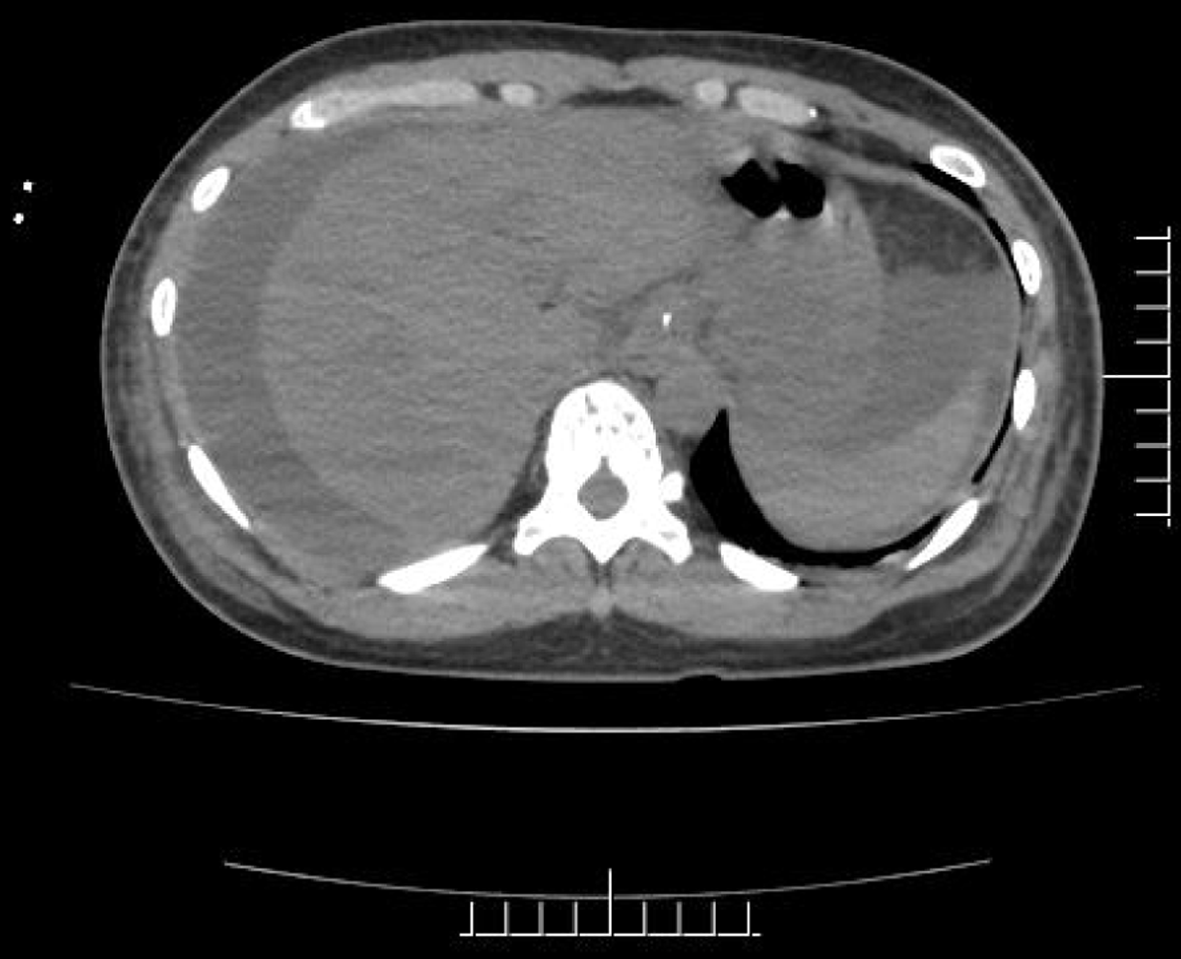

Figure 1 Abdominal computed tomography findings were diffuse hepatic lesions, veno-occlusive disease, cirrhosis, splenomegaly, ascites, and portal hypertension with collateral circulation.